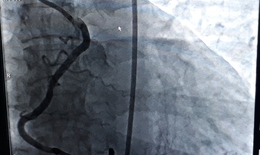

Y học 360 - 24/05/2025 11:51SKĐS - Trong nỗ lực mang đến giải pháp y tế tiên tiến cho người dân miền Trung, Bệnh viện Đa khoa TP Vinh đã ghi dấu ấn quan trọng khi trở thành đơn vị tuyến huyện đầu tiên ở Nghệ An triển khai thành công kỹ thuật can thiệp tim mạch qua hệ thống chụp DSA 2 bình diện hiện đại.

Can thiệp thành công ca bệnh có động mạch vành nhiều bất thường hiếm gặp

Thành tựu y khoa - 13/11/2018 07:09SKĐS - Ngày 12/11/2018, BS Nguyễn Văn Tân, Phó trưởng Khoa Tim mạch can thiệp - Cấp cứu, Bệnh viện Thống Nhất TP Hồ Chí Minh cho biết: Trong đợt chuyển giao kỹ thuật cho Đơn nguyên Tim mạch can thiệp cho Bệnh viện Đa khoa Phú Yên ông và các đồng nghiệp ở đây đã can thiệp thành công cho một bệnh nhân có động mạch vành phải xuất phát bất thường.